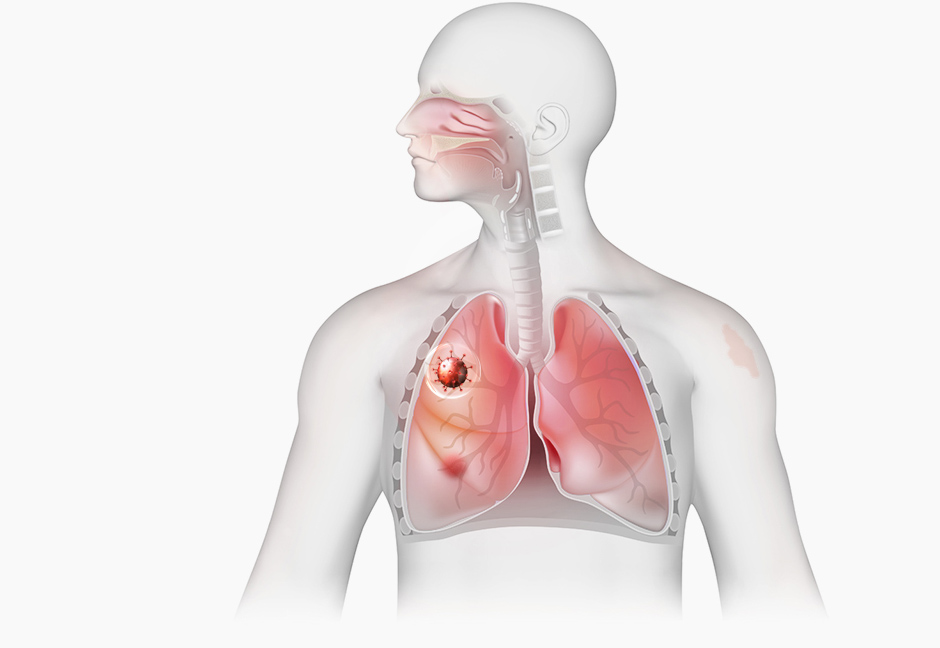

STEP 3

Healthy lungs

restore skin function

STEP 3

Healthy lungs

restore skin function